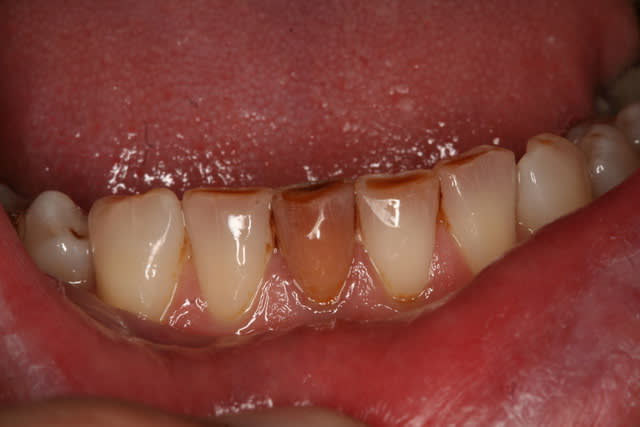

du orange

du marron

du jaune !

1/160 f20 Canon 350D avec capteur sale, Canon macro 100mm, flash MR14EX